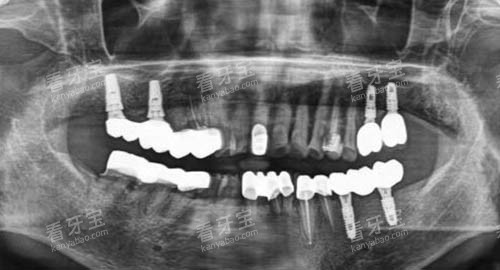

在牙齿检查方面,医院配备了智能化口腔全景机、口腔CT等新型设备。

智能化口腔全景机能够快速、更准地拍摄口腔全景图像,让医生超全了解患者口腔的整体情况;口腔CT则可以提供更详细的三维图像,帮助医生更比较准地诊断牙齿疾病和制定治疗方案。